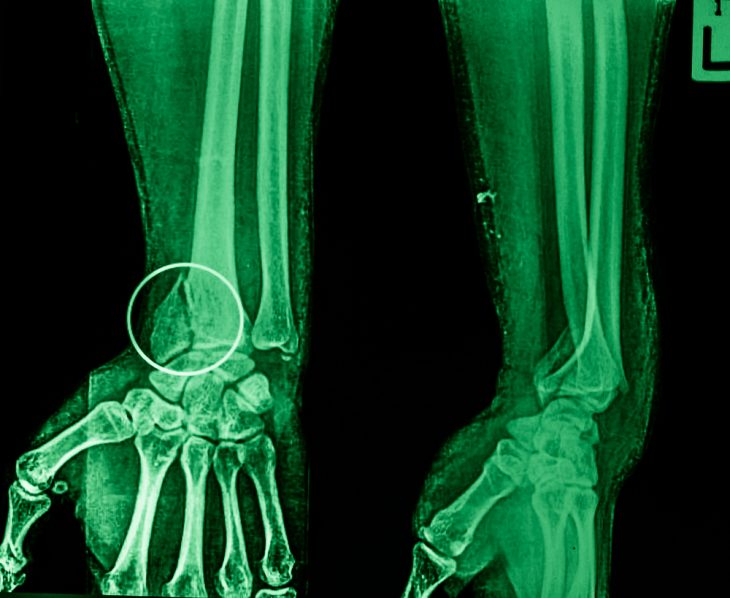

Для подтверждения диагноза и уточнения всех клинических данных о переломе проводится рентгенологическое обследование. При необходимости выполняется ангиография – радиография с введением контраста. Если диагностика вызывает затруднения, то проводится КТ.

Продолжительность иммобилизации зависит от многих факторов. Как правило, в среднем она длится 4-5 недель. При репозиции может возникать необходимость выполнения контрольных рентгеновских снимков на 10, 21 и 20 день после наложения гипса. Такие меры позволяют вовремя выявить и устранить путем новой репозиции или выполнения операции повторное смещение.